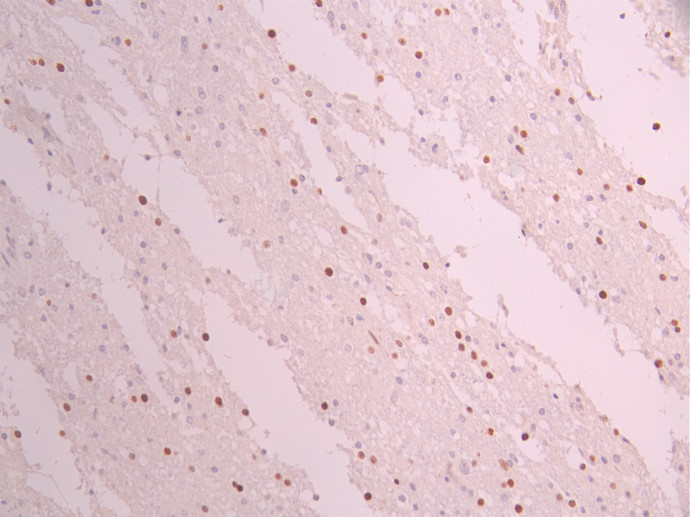

IHC image of CSB-RA172341A0HU diluted at 1:100 and staining in paraffin-embedded human glioma cancer performed on a Leica BondTM system. After dewaxing and hydration, antigen retrieval was mediated by high pressure in a citrate buffer (pH 6.0). Section was blocked with 10% normal goat serum 30min at RT. Then primary antibody (1% BSA) was incubated at 4°C overnight. The primary is detected by a Goat anti-rabbit polymer IgG labeled by HRP and visualized using 0.05% DAB.

IHC image of CSB-RA172341A0HU diluted at 1:100 and staining in paraffin-embedded human testis tissue performed on a Leica BondTM system. After dewaxing and hydration, antigen retrieval was mediated by high pressure in a citrate buffer (pH 6.0). Section was blocked with 10% normal goat serum 30min at RT. Then primary antibody (1% BSA) was incubated at 4°C overnight. The primary is detected by a Goat anti-rabbit polymer IgG labeled by HRP and visualized using 0.05% DAB.